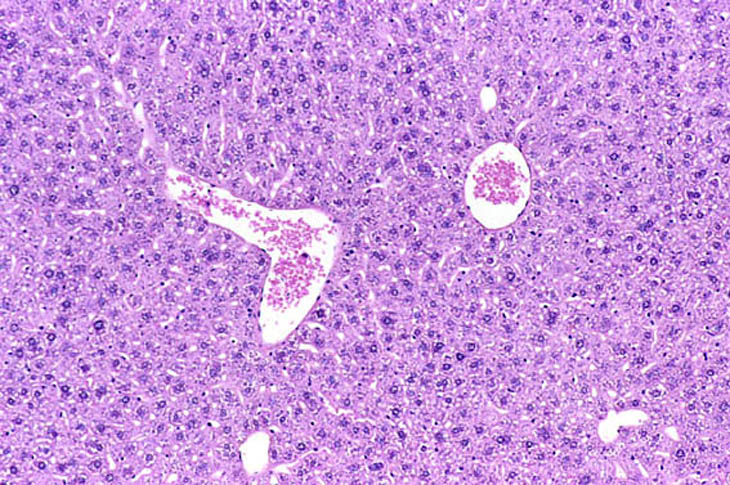

Immersion fixation in non-fasted mouse liver. Fixative was 10% NBF.